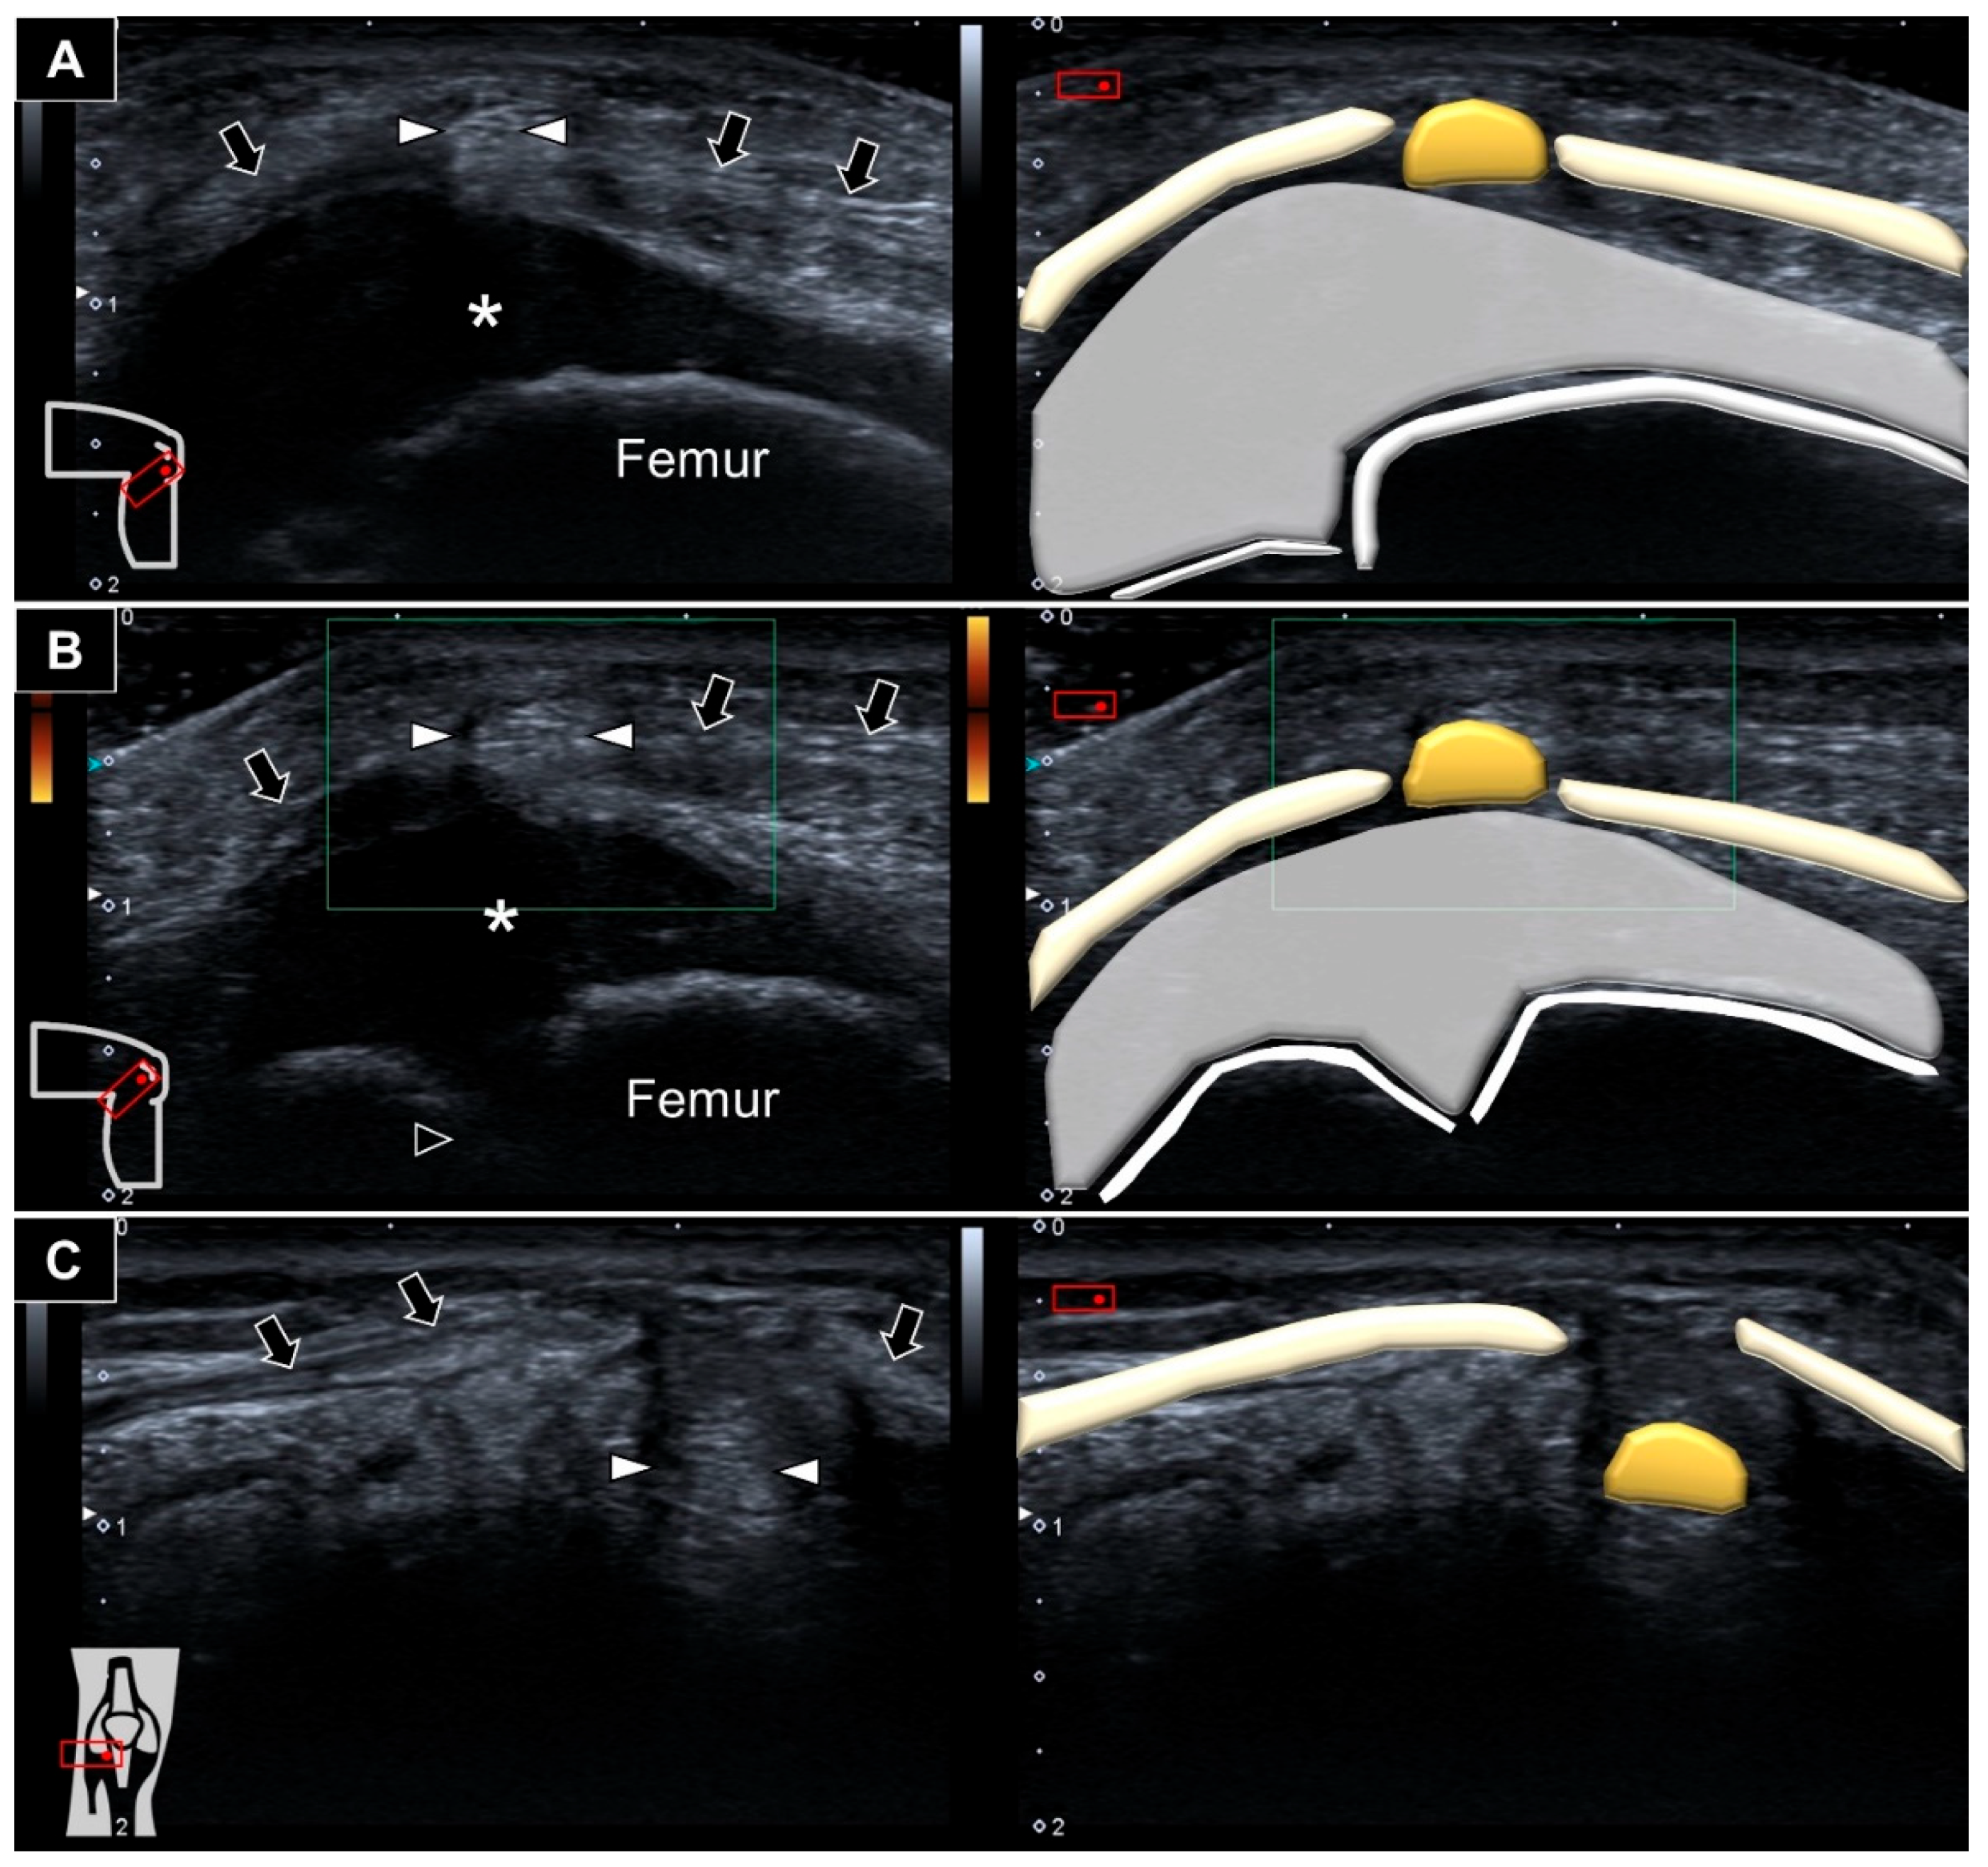

As no obvious mass was identified in the supine position, we then asked him to squat so as to make the mass more visible (Figure 2).

Figure 2. A mass (black arrow) was seen protruding from the lateral infrapatellar region when squatting.